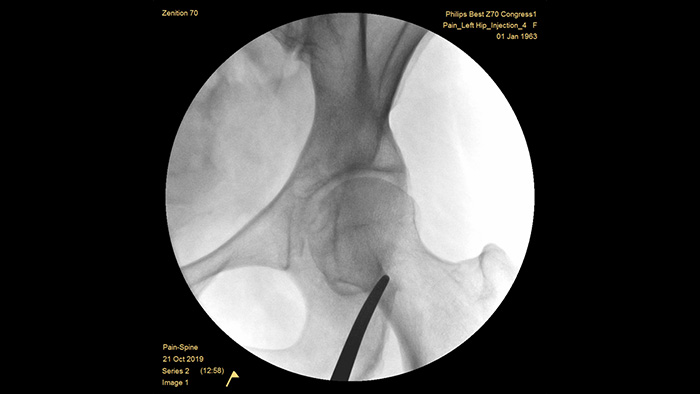

With our fourth generation Flat Detector systems, you gain exceptional image clarity of dense and complex anatomy. The compact form provides ample space and positioning ease for treating chronic pain in the joints. Our Position Memory2 increases first-time-right positioning to reduce scout images3 for efficient workflow in pain management cases. The Zenition 70 is available in two detector sizes: the FD 26 cm x 26 cm offers broad anatomical coverage, while the FD 21 cm x 21 cm provides ample space to work around patients.

Unique pre-configured pain management examination setting allows the users to easily set up the system during the interventional procedures for pain management.

MetalSmart automatically excludes metal artifacts caused by metal implants to provide higher image quality and efficient dose control for pain procedures and patients with metal implants, compared to systems without metal exclusion. BodySmart promotes first-time-right imaging and dose efficiency by automatically adapting the measuring field to the area of interest.

The optimal depth of the fully counterbalanced C-arm provides ample room to position around obese patients and image the lumbar spine and hip. It supports over the table positioning, even with tables that have a large base.